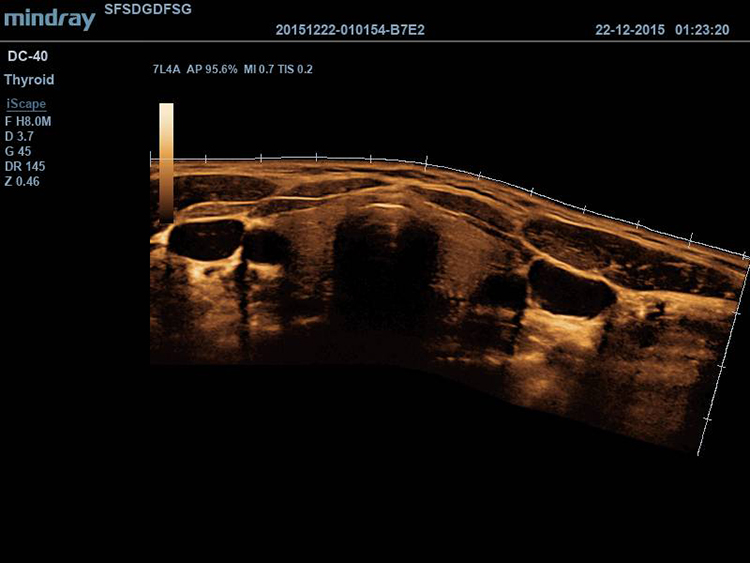

iScape (панорамная визуализация в реальном времени)

Расширяет визуализацию анатомических структур за счет последовательного панарамного отображения.

Линейный датчик Mindray 7L4A, (5.0/7.5/10.0MHz), 35 мм